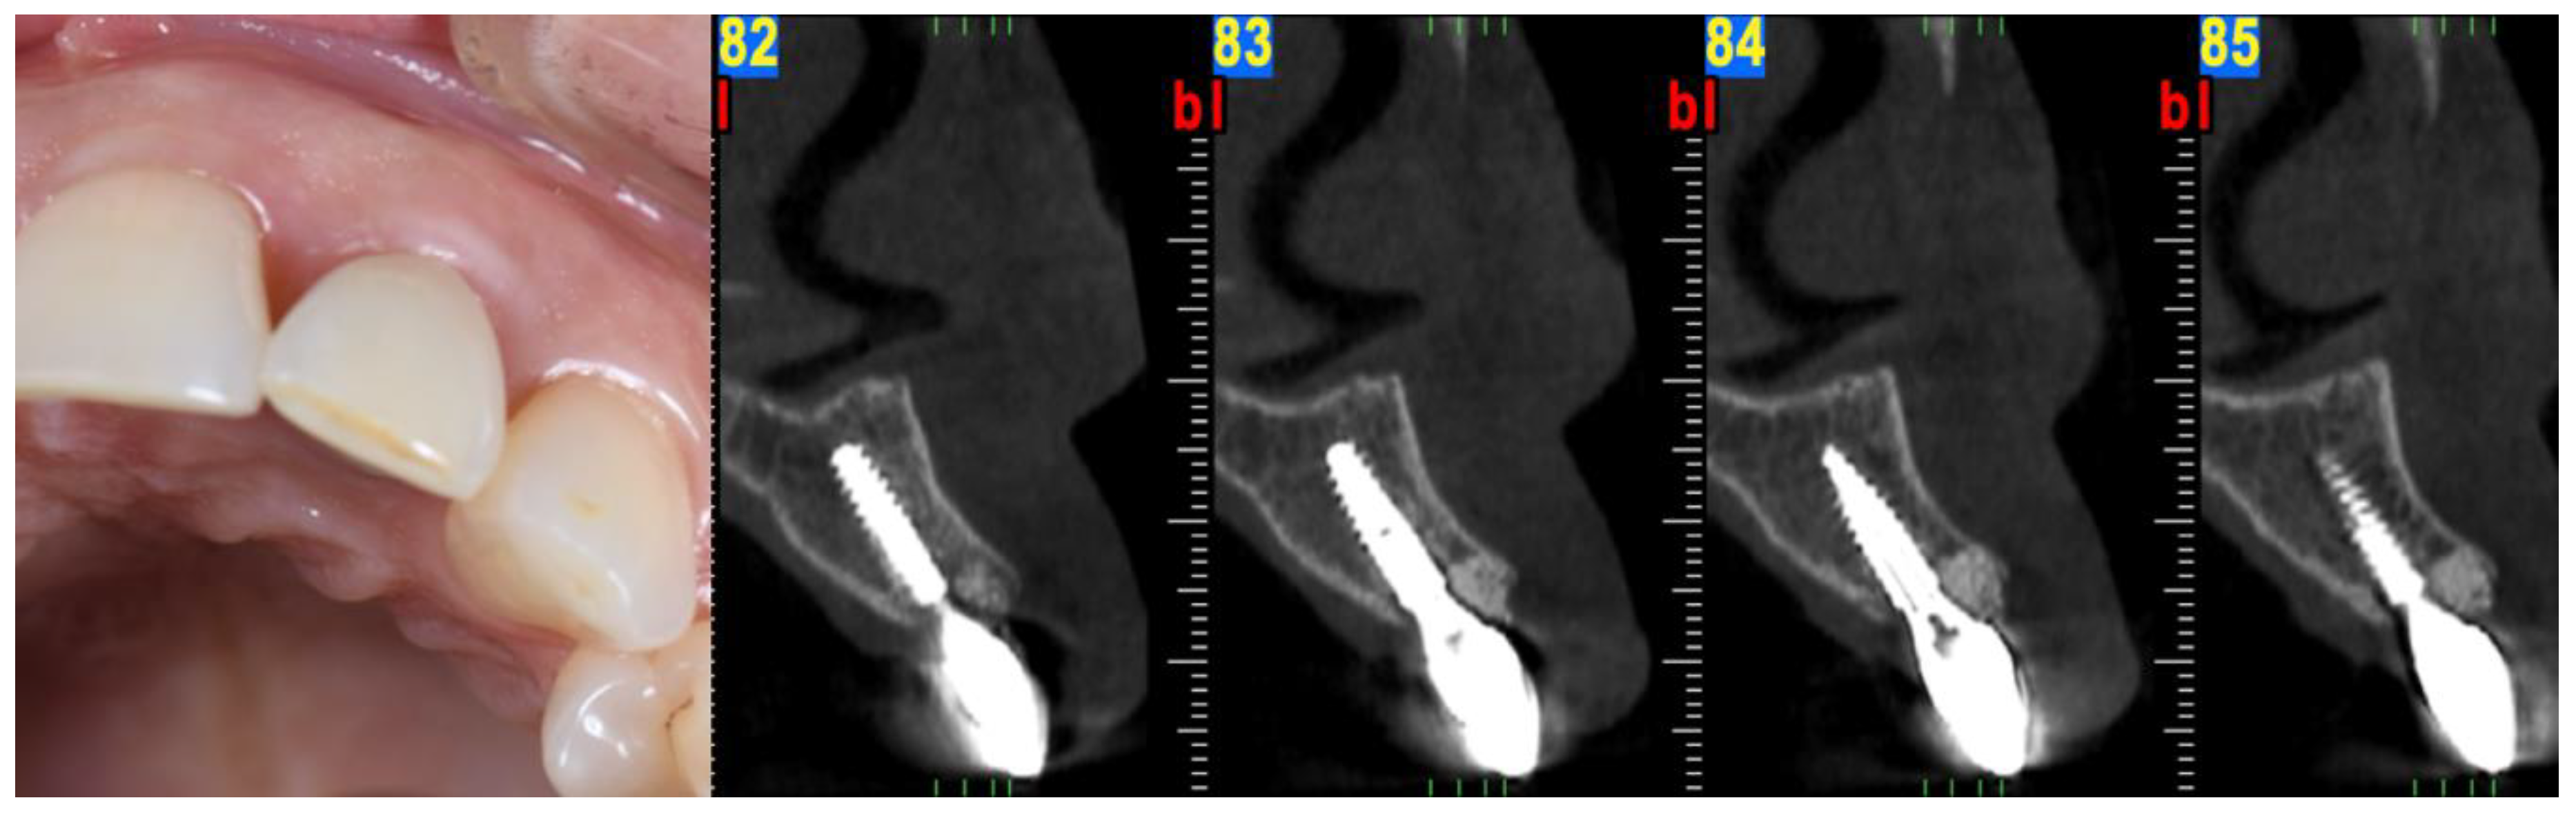

3. Case 2